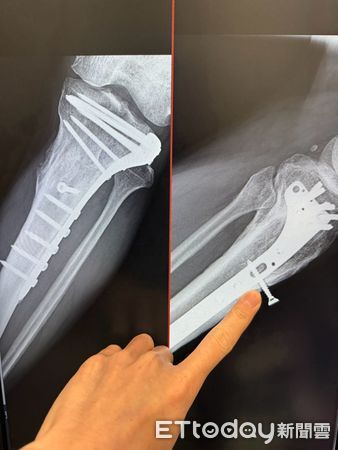

▲莊老先生左小腿有螺絲外露,經手術順利取出。(記者林東良翻攝,下同)

陳建宏醫師表示,莊老先生10年前因車禍造成左小腿骨折,當時接受「開放式復位併內固定手術」,以鋼板與螺絲固定癒合。多年來螺絲鬆動、慢慢往外推擠,竟穿透皮膚半截暴露在外。X光證實螺絲確為早年植入,醫師在「疼痛控制」下局部麻醉手術取出,過程順利。更令人驚訝的是,莊先生患有糖尿病,這段長期暴露的傷口居然未曾感染,堪稱不幸中大幸。